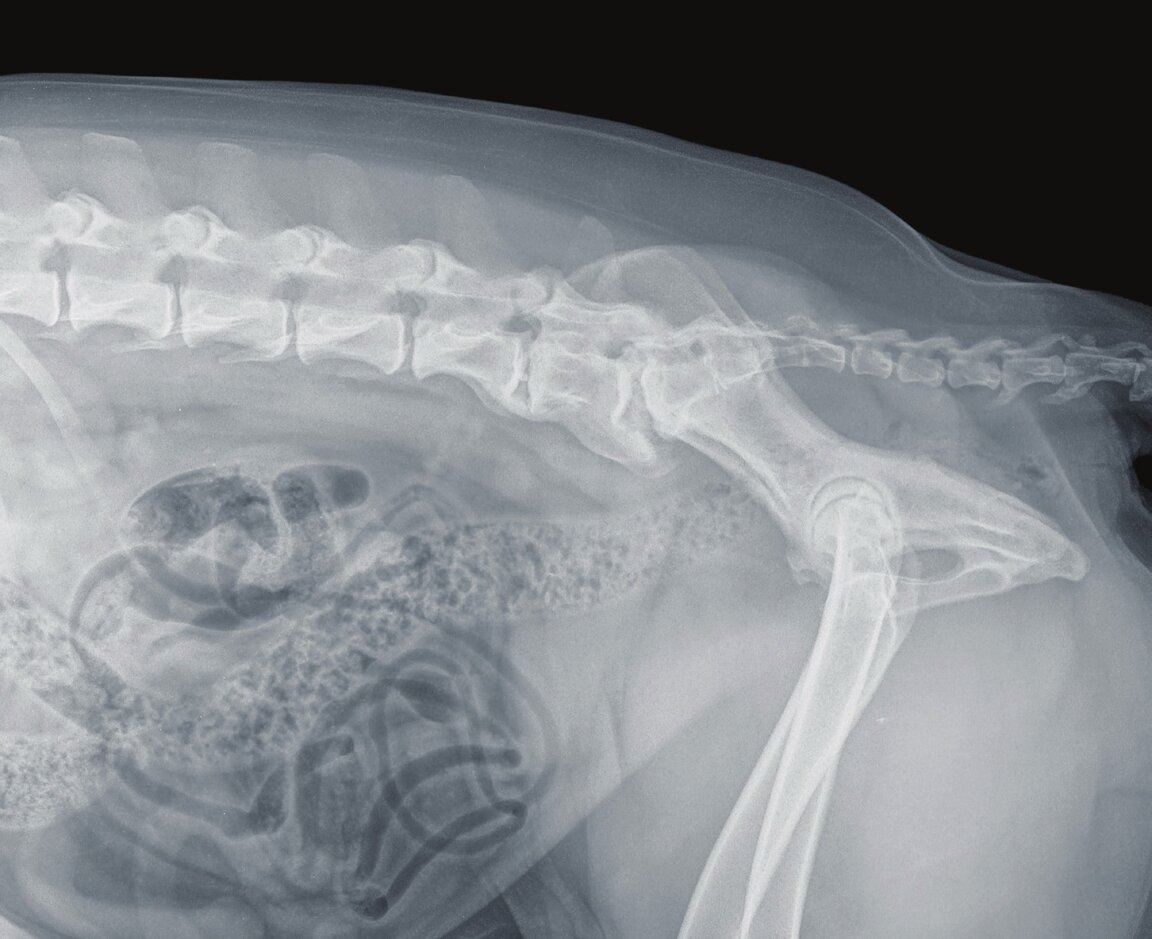

Röntgenbild der Hinterhand eines großen Hundes in Seitansicht: Die Darmschlingen und die starke Spondylose zwischen den beiden letzten Wirbeln und dem Kreuzbein sind gut sichtbar